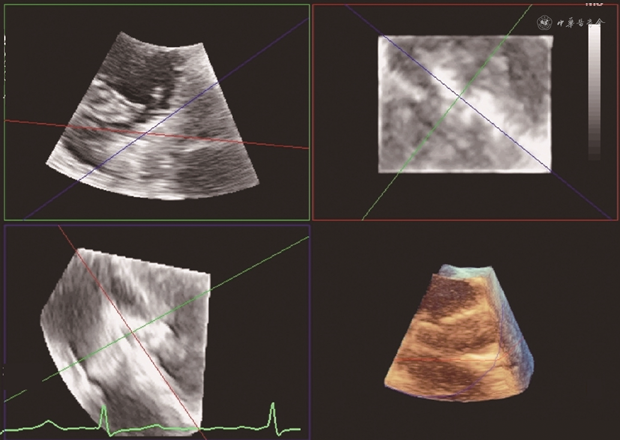

因三尖瓣位于心脏的前方,距离食管较远,且容易受到左心人工瓣膜以及夹子输送系统的声影影响,经食管超声探头位于食管中下段时,有可能不能提供足够清晰的图像显示夹子捕获三尖瓣。将食管超声探头送到胃部,并将食管探头前屈并向患者右侧旋转,在20°~60°范围内调整产生的经胃底短轴切面,避免了左心或输送系统的声影影响,可在一个二维平面同时显示三尖瓣三个瓣叶的结构,在此切面使用Biplane功能,可获得显示三尖瓣前瓣和后瓣的右心室长轴图像,可以辅助判断夹子进入右心室的深度,但不能为夹子捕获瓣叶提供引导。利用经胃底短轴图像进行三维图像重建,再利用Multiview进行图像分割重建,可精准获得和夹子重合的超声切面,显示夹子和瓣叶的关系,可用于引导瓣叶捕获和判断捕获程度(图6)。但因进行Multiview图像重建后,图像清晰度会有明显下降,因此对于重建前的二维超声图像有较高的质量要求。因此,经胃底短轴切面在经导管三尖瓣缘对缘修复手术中诸如夹子位置和方向的调整、瓣叶捕获判断、瓣叶夹持程度的判断等重要步骤中发挥关键作用[20]。如右心严重扩大或存在心脏转位,食管中段切面和经胃底短轴切面均无法提供满足引导要求的图像时,可使用心腔内超声[21]。

注:通过调整绿色方框和红色方框图像中的蓝线,使其分别和夹子臂和夹子输送系统重合,则可在蓝色方框中精确显示夹子和捕获瓣叶